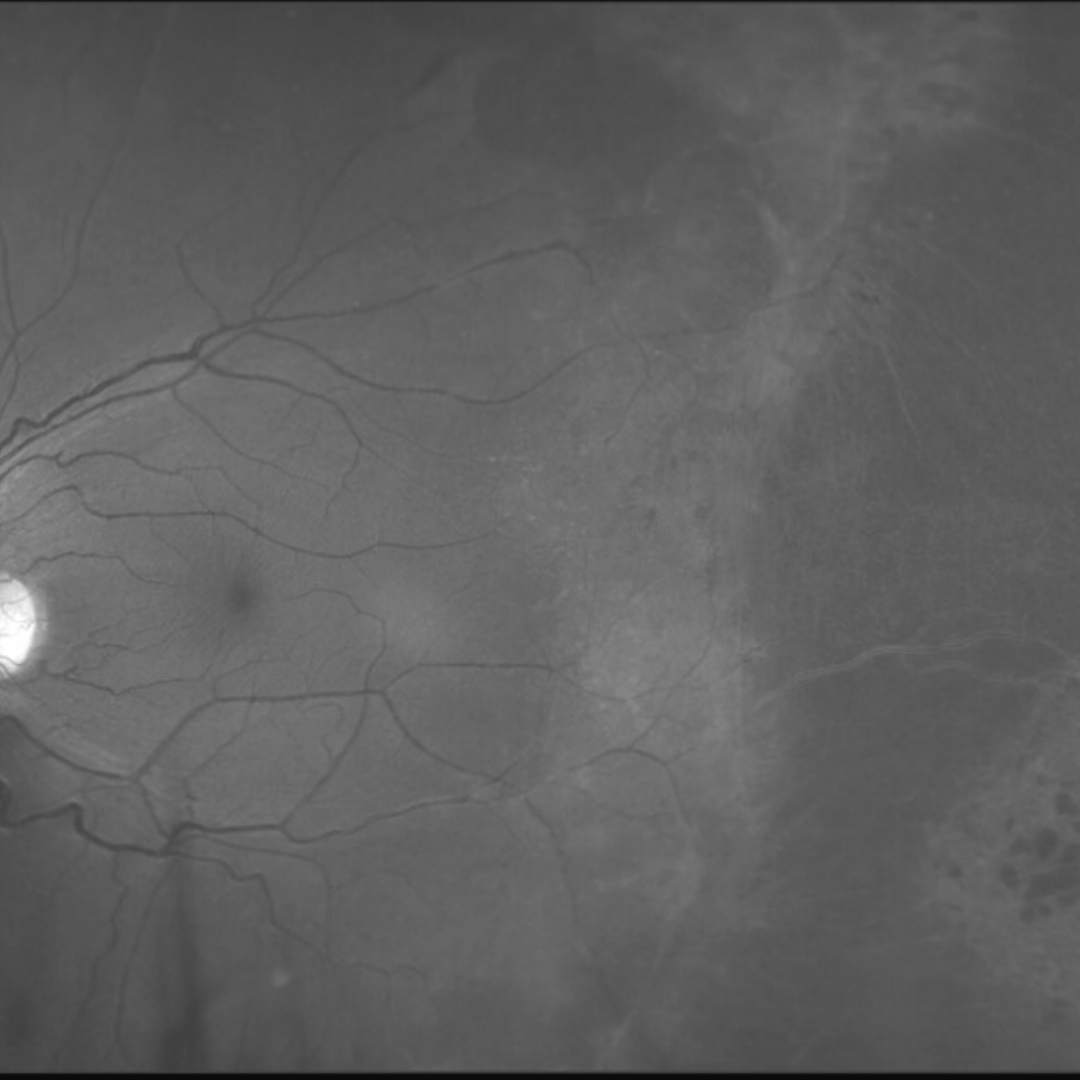

A 19-year-old Asian female who was born prematurely at approximately 6 months gestation and spent several weeks in an incubator. Her best-corrected visual acuity is 6/7.6-1 (20/25-1) in each eye. Her right eye is highly myopic (-8.25DS) and her left less so (-3.75 /-2.00 x 60).

Fundus photographs (right and left eye)

More infoRed free images (right and left eye)

More infoOptomap widefield and green separation image (right eye)

More infoOptomap widefield and green separation image (left eye)